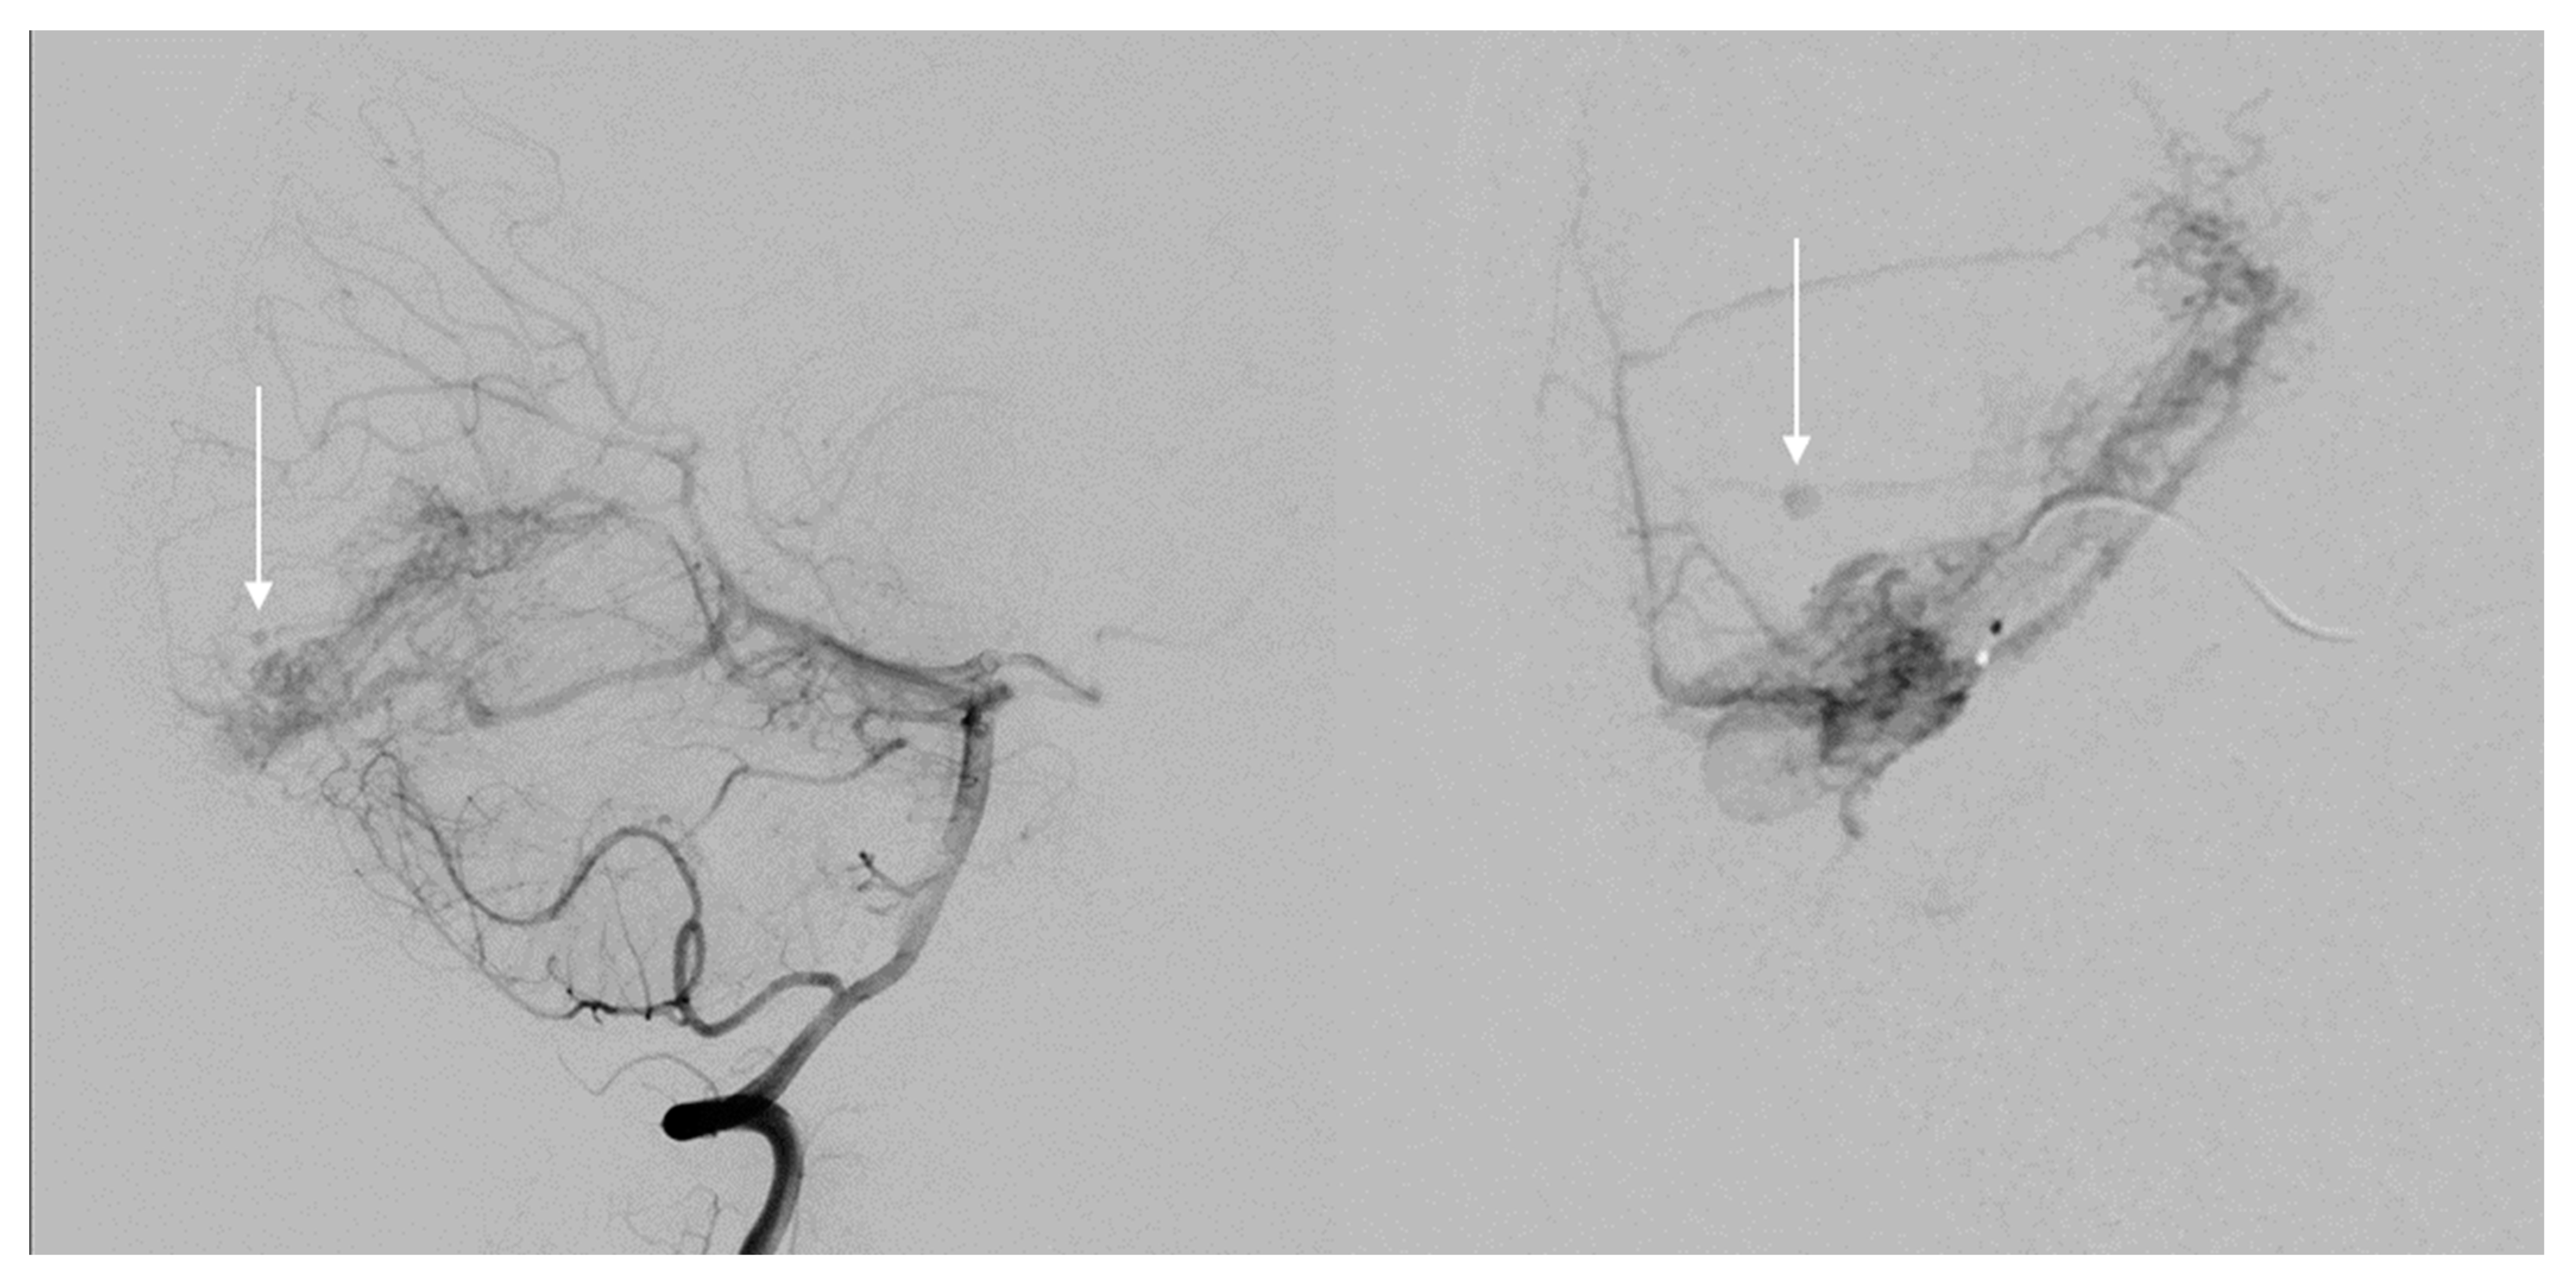

4.2. Endovascular Embolization

- Baharvahdat, H.; Blanc, R.; Fahed, R.; Pooyan, A.; Mowla, A.; Escalard, S.; Delvoye, F.; Desilles, J.P.; Redjem, H.; Ciccio, G.; et al. Endovascular treatment as the main approach for Spetzler–Martin grade III brain arteriovenous malformations. J. NeuroInterv. Surg. 2021, 13, 241–246. [Google Scholar] [CrossRef]